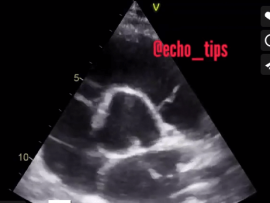

TEE shows Hugely dilated Left Atrium as a consequence of Rhematic Severe Mitral Stenosis, spontaneous Echo Contrast Grade IV “pre thrombus formation “ Mohammed Zidan, MBBCH, M.Sc Cardiology (Cardiology,..